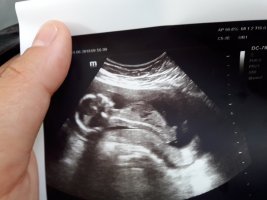

Benimde bakarmısınız lütfen doktor erkek dedi sonra gene erkek dedi kıza benziyor dedi yok yok erkek dedi bende sasrdm

Sizin bebeğinizin cinsiyeti erkeğe benziyor ama emin değilim. 20. haftaya doğru net olarak bebeğinizin cinsiyetini öğrenebilirsiniz.